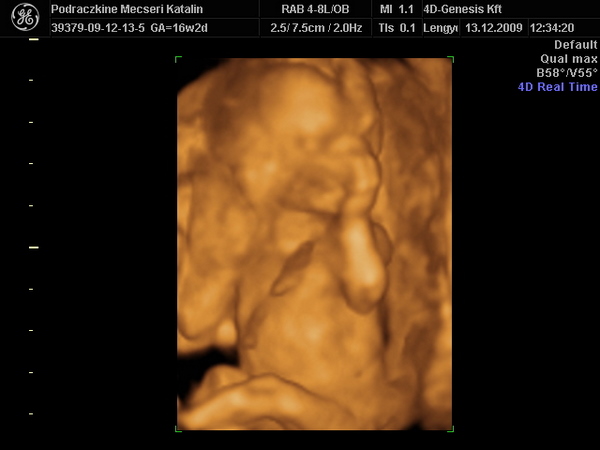

Kép Hát íme a kisfiam éppen alszik